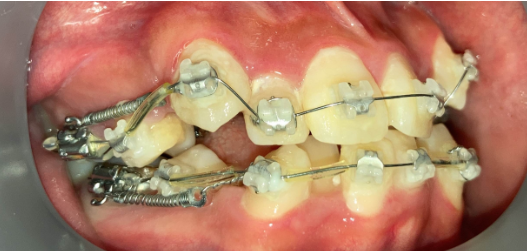

リカバリー症例1

他院の非抜歯矯正後、当院で再治療したケース

リカバリー症例の初診時の口腔内|奈良の矯正歯科

初診時

他院で非抜歯矯正を受け、歯並びは改善したものの、口元の突出感が残ったまま治療が終了。当院で精密検査を行った結果、上下4本の抜歯によるリカバリー治療が必要と判断しました。